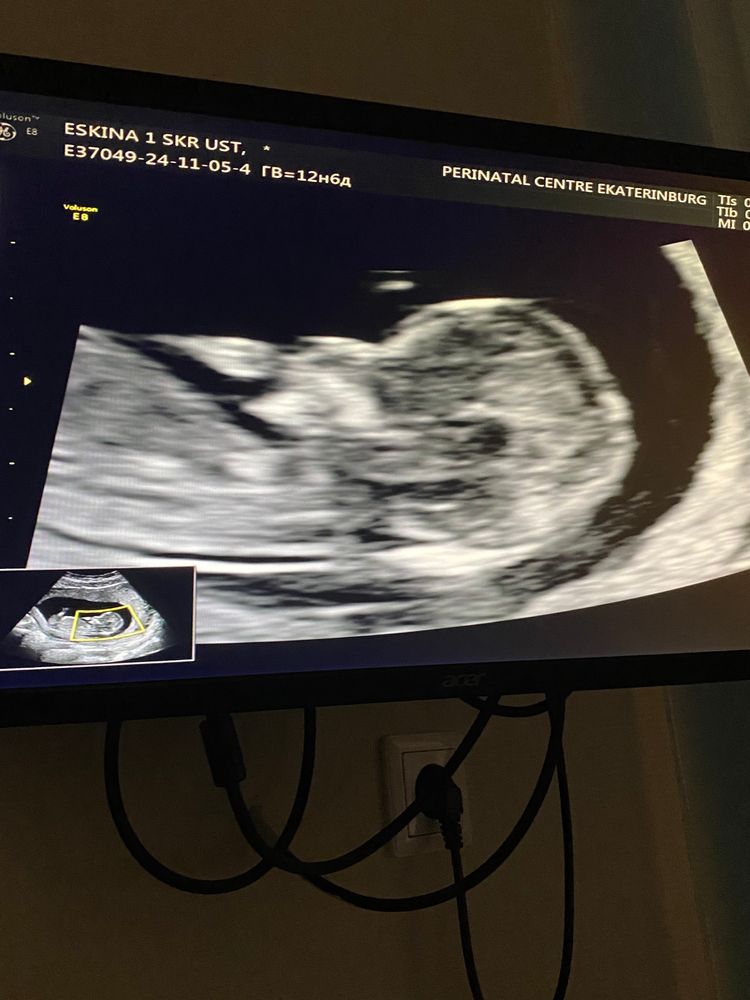

Эва в Благополучная беременность год Интересно кто будет?😅 Анализы, скрининги Знаю очень рано, но может кто нибудь сможет предположить Посмотрите еще 20 записей на эту тему Лучший ответ Анастасия У врача надо было спросить. Он сказал бы примерно 05.11.2024 Ответить Отменить Ответить Леди баг Девочка (судя по расположению полового бугорка, если это он на фото). 05.11.2024 Ответить Эва Леди баг, спасибо ☺️ 05.11.2024 Ответить Надя Мне кажется, девочка) 05.11.2024 Ответить Светлана А самое главное место не засняли ?)по головке тяжело определить 🫣 05.11.2024 Ответить Эва Светлана, разрешили только профиль сфотографировать 05.11.2024 Ответить Светлана Эва , а больше нет фото ?только это ? 05.11.2024 Ответить Эва Светлана, 05.11.2024 Ответить Светлана Эва , вот по этому фото мне кажется мальчик )))но это всего лишь моё предложение 💙 05.11.2024 Ответить За восходом Ребёнок отвернут,тут не видно 05.11.2024 Ответить Святая инквизиция Не видно и рано 05.11.2024 Ответить Беременность Ктр ниже нормы (новый пост, исправила данные) Чаты Беременных Выберите чат: Январята-2026 Февралята-2026 Мартята-2026 Апрелята-2026 Майчата-2026 Июнята-2026 Июлята-2026 Августята-2026